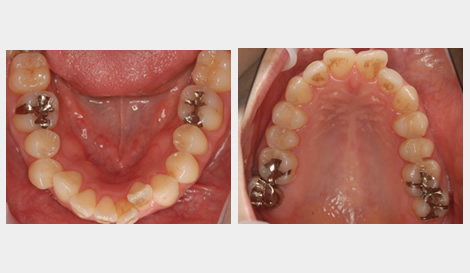

エステティックラインとは、横から見た時に鼻と顎を結んだ口元のラインのことです。

「美しい口元の基準」とも呼ばれ、矯正治療の基準になります。

このケースでは、出歯により気になるエステティックラインを、

約1年半ほどの矯正期間で改善し、美しいラインを実現しました。